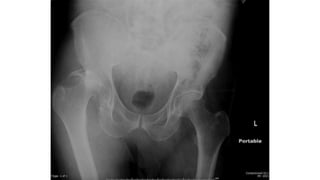

• #3 Posterior hip dislocation